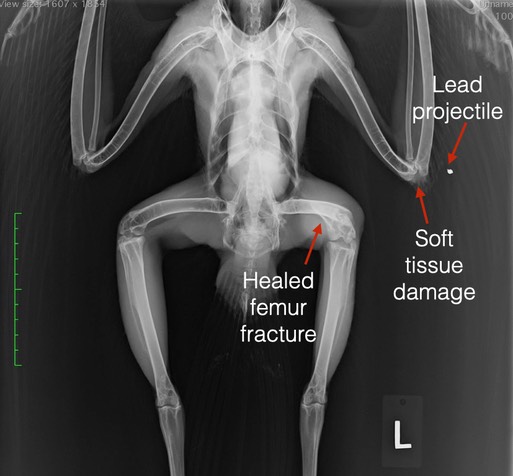

A radiograph clarified the situation. It is unlikely that the projectile visible in the radiograph below caused both the elbow and feather damage. There must have been at least one additional projectile. We can conclude that the projectile is lead because of its deformed shape. Hopefully the injury to the elbow is superficial and the hawk will be releasable. Before then he will have to go through a molt and replace the broken feathers.

Also visible in the radiograph is a healed femur fracture in the hawk’s left leg. The hawk had managed to recover from a broken leg, before he was shot. His left leg is significantly shorter than his right leg, but the left foot is fully functional. There is some atrophy of muscle in the left leg which probably have occurred while the fracture was healing and the hawk was not able to use the leg. One thing’s for sure, this is one tough hawk.